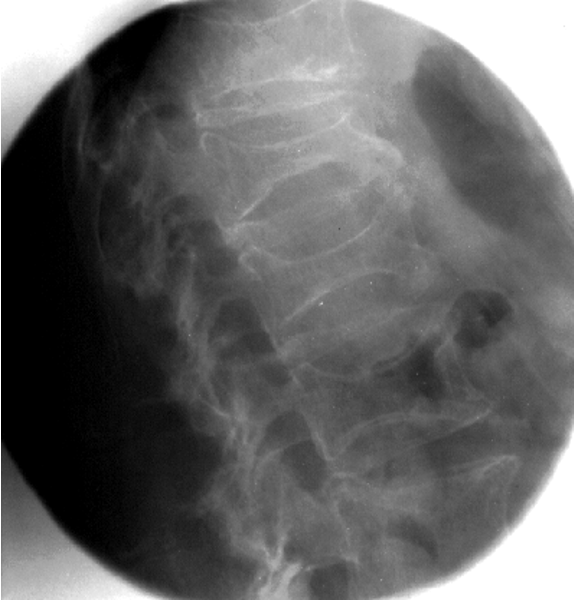

Patient Factors

•Patient’s size, shape, and physical condition greatly influence the required radiographic technique

–Size and shape (body habitus)

–Anatomy density (thickness)

–Pathology

–Composition

•Chest v. Abdomen

Composition

•Measuring the thickness of a part doesn’t automatically release the technologist from exercising some additional judgment when selecting the proper technical factors

–Ex: the chest and the abdomen may have the same thickness, but vary considerably in composition

•Chest:

–Lung (air), Ribs (bone), heart (muscle)

–High subject contrast: mostly black and white, with some grays in between

•Abdomen:

–Stomach, bowels, liver, kidney, spleen, pancreas, diaphragm, urinary bladder, etc.

–Muscle, fat, and water very similar in composition

–Many shades of gray

Radiopaque vs. Radiolucent

•Radiopaque

–Difficult to penetrate

–Bone, metal

•Radiolucent

–Easy to penetrate

–Air, soft tissue

Pathology

–Type, size, and composition will influence radiographic technique

–Obtaining good patient history and previous exams will help assessment

–Destructive process causing tissue to be more radiolucent. Ex: osteoporosis

–Constructive in increase mass density and composition. Ex: osteopetrosis